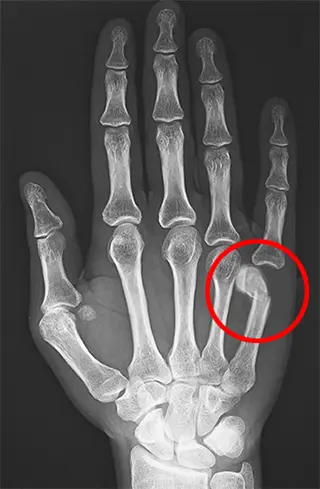

Fractures of the Hand and Fingers

Boxer’s Fracture

Physical examination by a specialist can often suggest a break based on pain location, swelling, deformity, and loss of function. However, X-rays confirm the diagnosis and show exactly how the bone is broken, which is essential for planning the right treatment.